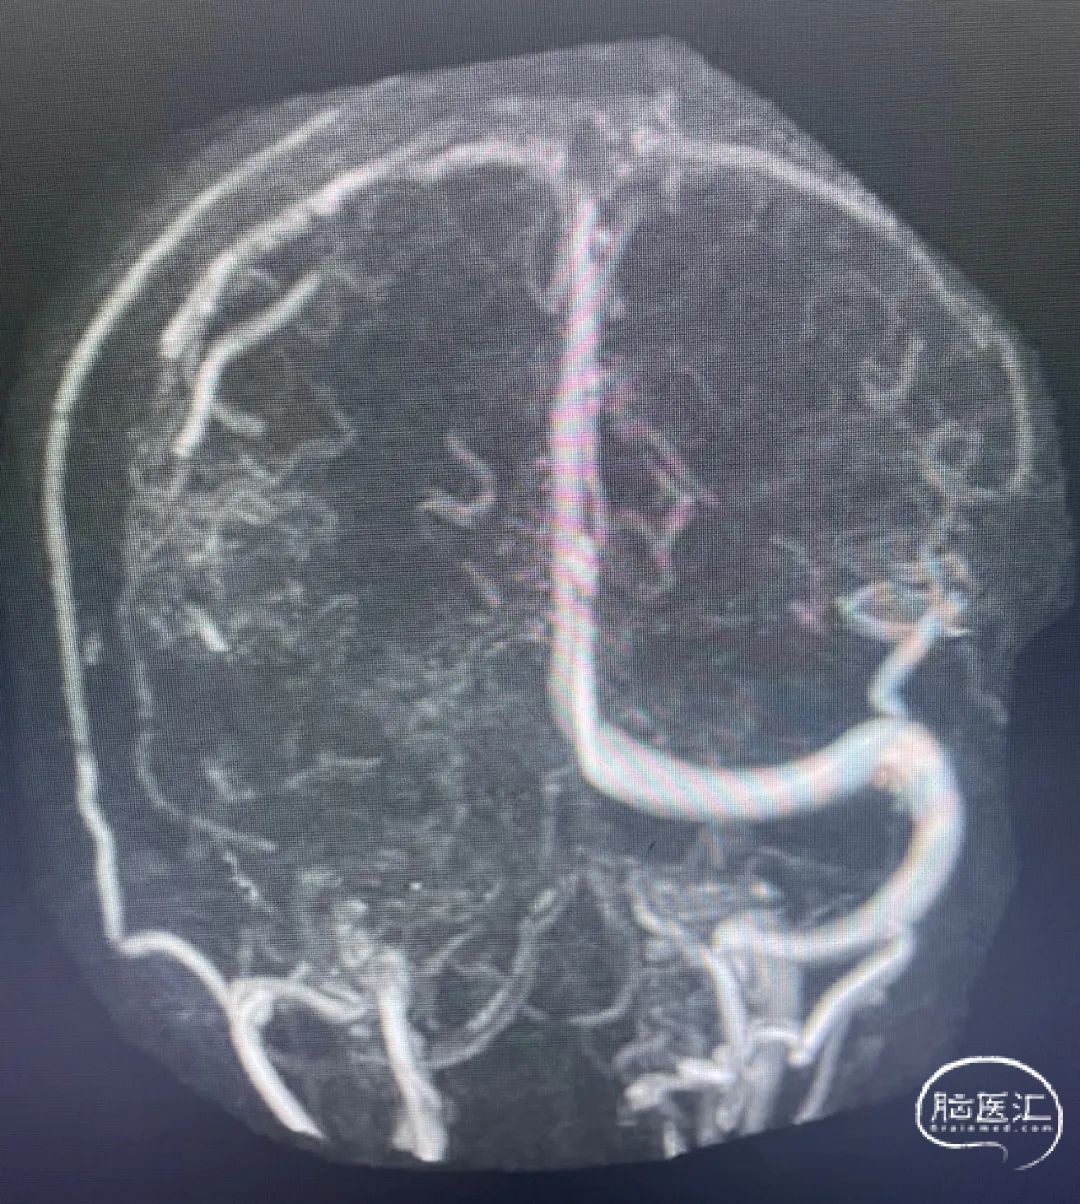

术后影像

术后造影显示上矢状窦较前明显改善。

术前上矢状窦闭塞

术后上矢状窦再通